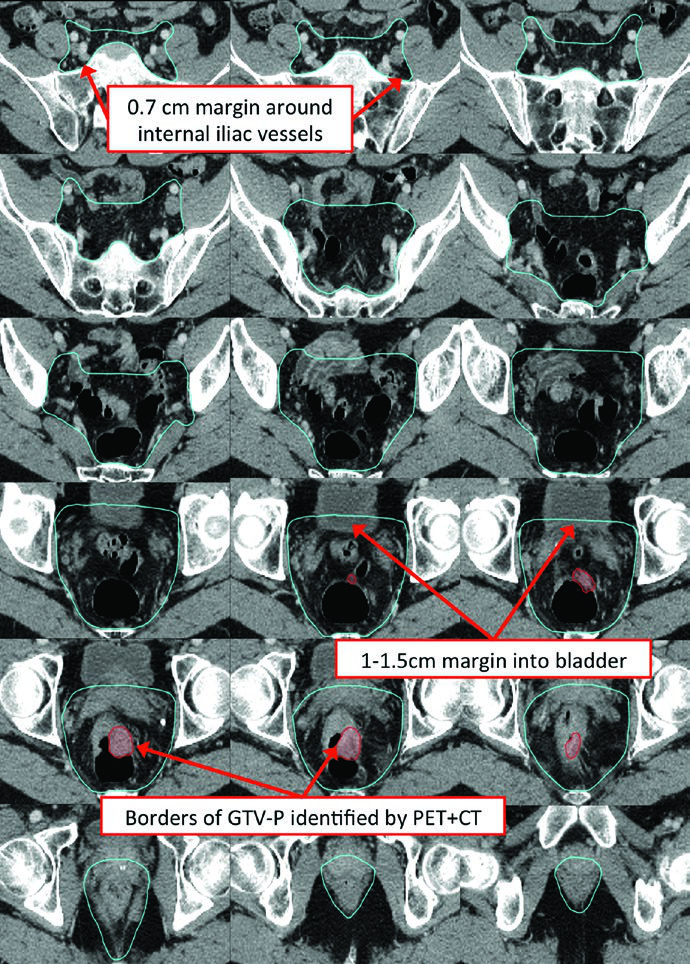

O CTV de alto risco (CTV-HR) deve incluir o GTV com margem mínima de 1,5 a 2 cm superior e inferiormente, além de todo o reto, mesorreto e espaço pré-sacral. Para linfonodos ilíacos externos ou inguinais macroscopicamente comprometidos, a margem GTV-para-CTV deve ser de no mínimo 10 a 15 mm. Em tumores T4, adiciona-se margem de 1 a 2 cm nos órgãos adjacentes invadidos (bexiga, próstata, cérvix).

| CTV-HR | GTV-P e GTV-N com margem de 1,5-2 cm superior e inferiormente, excluindo osso, músculo e ar não envolvidos. Margem mínima de 10-15 mm para linfonodos ilíacos externos ou inguinais macroscópicos. Inclusão de reto, mesorreto e espaço pré-sacral no plano axial. Margem de 1-2 cm em órgãos adjacentes para T4 |

| CTV-SR | CTV-HR + mesorreto completo + linfonodos ilíacos internos bilaterais. Ilíacos externos e obturadores para T4 com invasão anterior. Inguinais para tumores com extensão para o canal anal. Superior: interespaço L5/S1 ou 2 cm acima da doença macroscópica. Inferior: assoalho pélvico ou 2 cm abaixo da doença. Margem de 0,7 cm ao redor dos vasos ilíacos internos. Margem anterior de 1-1,5 cm na bexiga |

| Pelve média | Inclui reto, mesorreto, região dos ilíacos internos e 1 cm de margem na bexiga. Posterolateral até musculatura ou osso da parede pélvica. Anterior: pelo menos 1 cm na bexiga posterior. Margem de 7-8 mm em tecido mole ao redor dos vasos ilíacos internos |